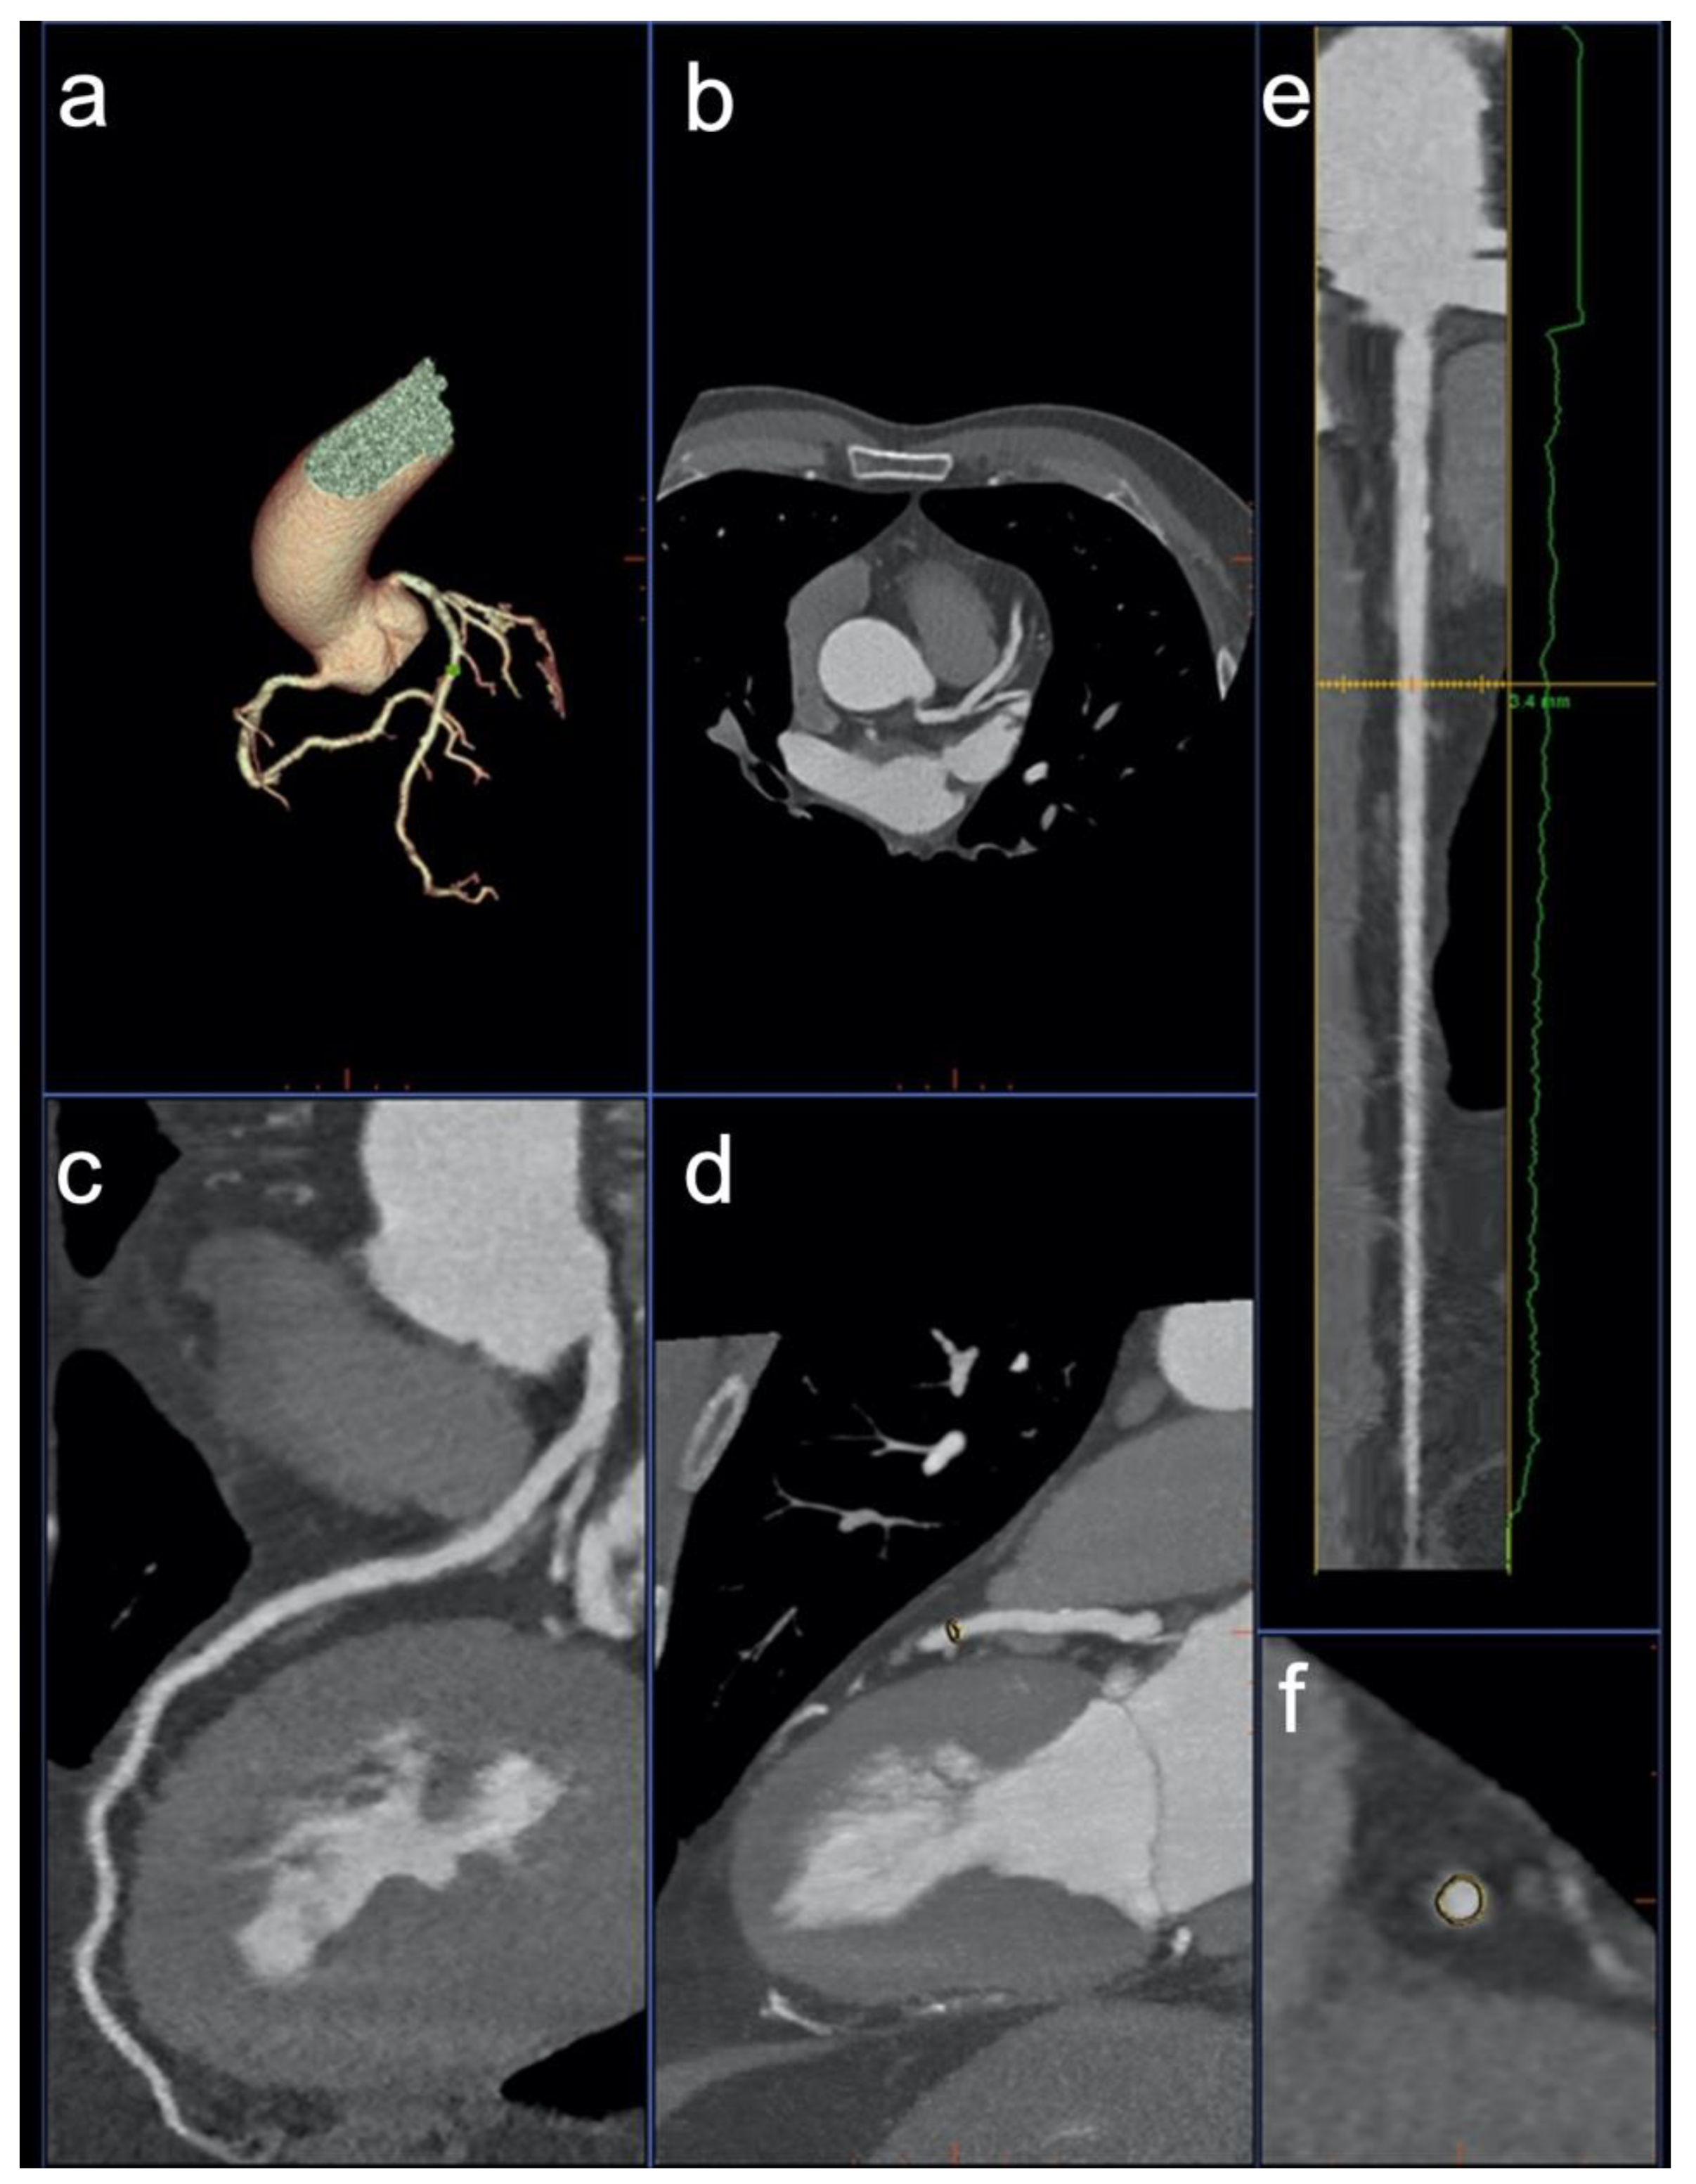

2.3. Image Post Processing—Group 1

2.5. Image Post Processing—Group 2